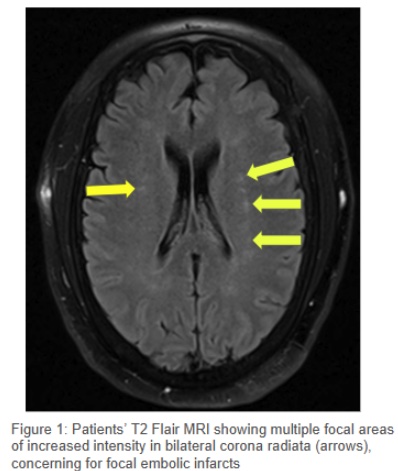

Case Presentation: A 56-year-old man was found unresponsive at home during a wellness check. Paraphernalia and the condition of other patients at the scene suggested a drug overdose. In the emergency department, his vital signs were HR 136 bpm, BP 164/90 mmHg, RR 22, and SpO2 94% on room air. Due to severe agitation, physical restraints and one-time doses of haloperidol and lorazepam were administered. A urine drug screen was positive for cocaine. Initial labs revealed AKI (creatinine 2.32 mg/dL), rhabdomyolysis (CK >30,000 U/L), acute liver injury (AST 557 U/L, ALT 150 U/L), elevated troponin I (5.3 ng/mL), and hyperkalemia (K 6.3 mmol/L) with peaked T waves on ECG. Treatment included 3L IV fluids, calcium gluconate, and arrangements for continuous renal replacement therapy (CRRT). A CT head without contrast showed no acute findings. Chest X-ray revealed pulmonary edema, and BNP was elevated (1,720 pg/mL), suggesting acute decompensated heart failure. He developed hypoxemia (SpO2 70%) with apneic episodes and fluctuating somnolence and agitation. After failed attempts at supplemental oxygen, he was intubated and sedated. With treatment, renal function slowly improved, troponin resolved in a pattern consistent with type 2 NSTEMI, liver injury normalized, and hyperkalemia corrected with CRRT. After extubation, he was unable to move his left arm. MRI of the left brachial plexus revealed acute plexopathy, and brain MRI showed bilateral embolic infarcts. Transesophageal echocardiography (TEE) identified a 0.96 x 0.74 cm lesion on the aortic valve, consistent with a sessile fibroelastoma. Cardiology and cardiothoracic surgery recommended open-heart surgery, but the patient elected to pursue treatment in his home state. He was discharged to a suitable facility.